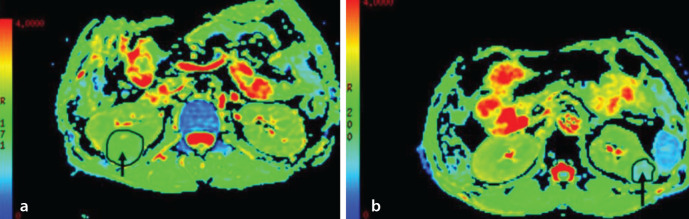

Methods: Sixty-eight patients with ccRCC and 18 patients with RAMF were retrospectively studied. For DKI and apparent diffusion coefficient (ADC), respiratory-triggered echo-planar imaging sequences were acquired in the axial plane (three b-values: 0, 1000, 2000 s/mm2; one b-value: 2000 s/mm2). Mean diffusivity (MD), fractional anisotropy (FA), mean kurtosis (MK), kurtosis anisotropy (KA), radial kurtosis (RK), and ADC were evaluated. The diagnostic efficacy of various diffusion parameters in predicting ccRCC and RAMF was compared.

Results: The ADC and MD values of ccRCCs were higher than those of RAMFs (P < 0.05), whereas comparable FA, MK, and KA values were observed between ccRCCs and RAMFs (P > 0.05). Moreover, the RK values of RAMFs were higher than those of ccRCCs (P < 0.05). Receiver operating characteristic (ROC) curve analyses showed that MD values had the highest diagnostic efficacy in differentiating ccRCCs from RAMFs. In pairwise comparisons of ROC curves and diagnostic efficacy, DKI parameters demonstrated better diagnostic accuracy than ADC in differentiating between ccRCCs and RAMFs (P < 0.05).